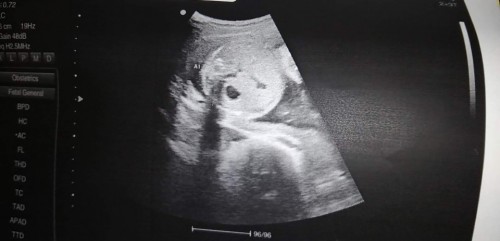

ซาวด์มาตอน24w4d แต่หมอไม่บอกอะไรเลยค่ะอยากรู้ว่าในรูปคือส่วนไหนบ้างคะ เด็กปกติไหมคะ นน.714 กรัมค่ะ

ปกติคุณแม่บำรุงดีใช่ไหมคะเนี้ย ปกติ24วีคตามเกณฑ์ต้อง600กรัม น้องสมบูรณ์ดีเลยค่ะ